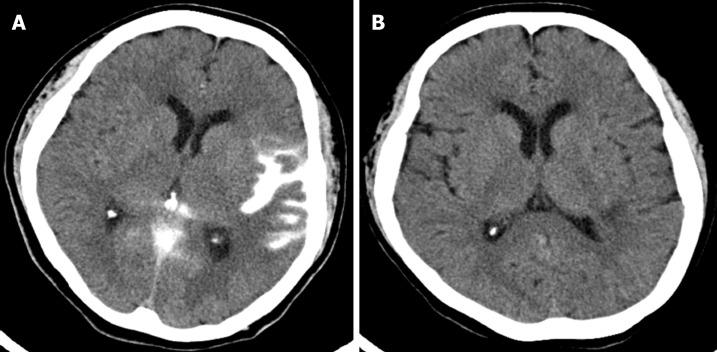

A 63-year-old woman presented to the emergency department with sudden neurologic symptoms of right hemiparesis and global aphasia. The initial National Institutes of Health Stroke Scale score was 15. Computed tomography (CT) and CT angiography revealed hyperacute infarction and emergent arterial occlusion of the left middle cerebral artery M2-3 portion. During endovascular mechanical thrombectomy, arterial rupture occurred. The patient's vital signs were stable, but delayed angiography showed persistent active bleeding. Therefore, selective embolization of the injured artery was performed using gelfoam. Subsequent left vertebral and internal carotid angiography was performed to confirm hemostasis. A localized subarachnoid hemorrhage (SAH) was confirmed on a follow-up CT scan. A repeated CT scan after 12 d showed resolution of the SAH, and rebleeding did not occur.

一名63岁女性因突发右侧偏瘫和完全性失语的神经系统症状就诊于急诊科。最初的美国国立卫生研究院卒中量表评分为15分。计算机断层扫描(CT)和CT血管造影显示超急性梗死以及左大脑中动脉M2 - 3段的急性动脉闭塞。在血管内机械取栓过程中,发生了动脉破裂。患者生命体征稳定,但延迟血管造影显示持续活动性出血。因此,使用明胶海绵对受损动脉进行了选择性栓塞。随后进行了左侧椎动脉和颈内动脉血管造影以确认止血情况。随访CT扫描证实有局限性蛛网膜下腔出血(SAH)。12天后重复CT扫描显示SAH已消退,且未发生再出血。